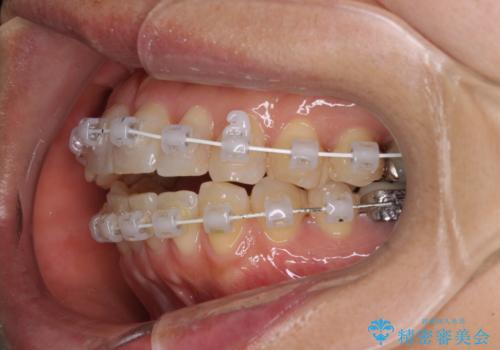

- 矯正装置

- 審美装置

- 治療期間

- 1年10ヶ月

- 前歯のデコボコを気にして来院された患者様です。

インビザラインでもワイヤー装置でも対応可能であったので、両者のデメリットをご説明し、選択していただくことになりました。

マウスピース矯正の装着時間の長さや自己管理の重要性を煩わしいと感じられ、低依存で確実に治療ができるワイヤー矯正を選択されました。

舌突出癖により、上下前歯がなかなか接触せずに治療期間を要しましたが、舌のトレーニングにより無事に治療を終えることができました。